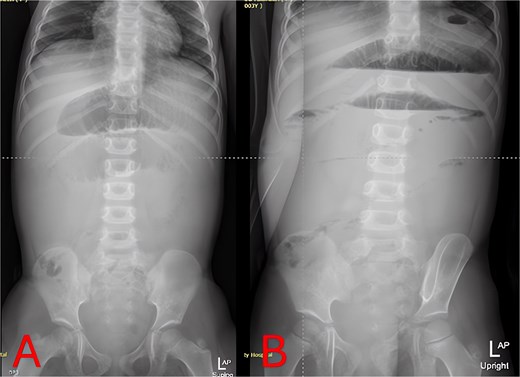

Plain abdominal radiographs revealed centrally dilated small-bowel loops with paucity of distal gas (Fig. 1A) and multiple air–fluid levels without free subdiaphragmatic air (Fig. 1B), consistent with mechanical small-bowel obstruction. Initial management, including nasogastric decompression, nil per os (NPO) status, and intravenous ceftriaxone (75 mg/kg once daily) plus vancomycin (15 mg/kg every 6 hours), failed to improve radiographic findings after 24 hours (Fig. 2A and B), prompting further imaging.

Admission abdominal radiographs (composite). (A) Supine abdominal X-ray on presentation demonstrating central small-bowel dilation and paucity of distal gas. (B) Upright abdominal X-ray on presentation showing multiple small-bowel air-fluid levels without free air.